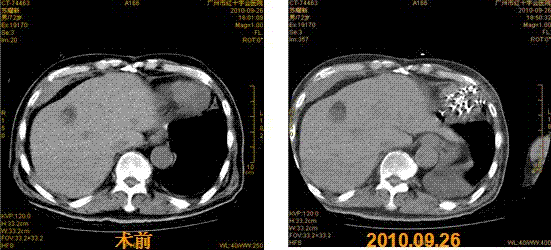

2013年8月底,经朋友介绍慕名来到广州中医药大学金沙洲医院肿瘤中心接受WB-1全身热疗(肿瘤深部全身热疗),根据患者的情况,专家团会诊后采用全身热疗结合基因治疗,1个疗程后,肺部肿瘤缩小42.7%,疼痛、咳嗽、腹水等症状全面消失,白细胞上升到正常水平。近期回访,患者身体状况良好,达到带瘤生存。